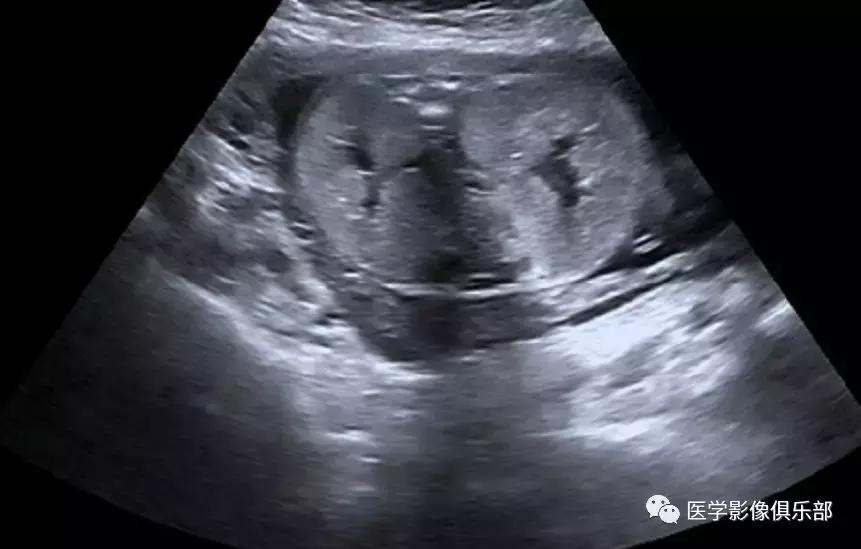

[病例举例]:常规产科超声显示胎龄26周胎儿畸形。

胎儿超声显示双肾明显增大,回声增强,羊水量较少。